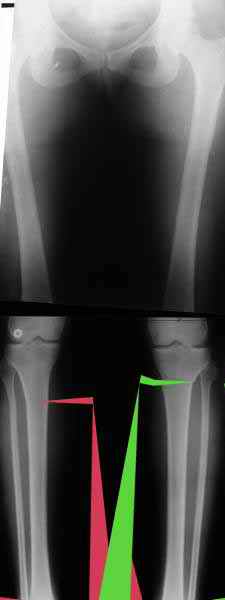

Судя по снимку у девушки имеется внутренняя установка надколенников...

Как у нее с торсионным статусом? Бедро? Голень? КТ? Торсиометры? А то, куда будут

смотреть надколенники после вашей коррекции - тоже существенный

косметический момент. Или не так?

AVM> Судя по снимку у девушки имеется внутренняя установка надколенников...

AVM> Как у нее с торсионным статусом? Бедро? Голень? КТ? Торсиометры?

Похоже, немного есть. Думаю пренебречь.

AC> Вот, с учетом и без учета, и на разных уровнях...

Из приведнной схемы не совсеим понял что означают разноцветные линии.

И зачем латерализация периферического фрагмента. Я всегда делаю медиализацию. См схему. И для данного случая медиализация подходит как нельзя лучше.

a> Из приведнной схемы не совсеим понял что означают разноцветные линии.

Черные - это нынешняя механическая ось. Красные - это планируемая правильная ось.

a> И зачем латерализация периферического фрагмента.

;-) Читайте Палея. Стр. 114-115.

a> Я всегда делаю медиализацию. См схему. И для данного случая

Медиализация - это чисто эстетический прием, как я понимаю. Поскольку если делать остеотомию ниже вершины деформации, для восстановления оси надо делать смещение по ширине, в данном случае как раз латерализацию.

А вот на схемке без осей - там на разных уровнях (который правильнее?) устранение варуса чисто открытым клином без медиализации-латерализации. Если как-то так сделать - этого недостаточно будет?